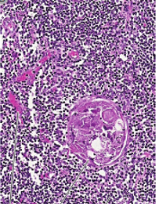

DESCRIBE ESTA IMÁGEN Y EN QUE PARTE SE ENCUENTRAN LOS LINFOCITOS T

ROJO: VASOS SANGUÍNEOS

AZUL: CORPÚSCULO DE HASSALL

CÉLULAS PEQUEÑAS TEÑIDAS DE AZUL SON LINFOCTIOS T EN DESARROLLO (TIMOCITOS)

MENCIONA QUE CÉLULAS CONFORMAN LA CORTEZA Y LA MÉDULA

CORTEZA: LINFOCITOS T Y CÉLULAS EPITELIALES DE LA CORTEZA

MÉDULA: CÉLULAS EPITELIALES DE LA MÉDULA, LINFOCITOS T, MACRÓFAGOS, CÉLULAS DENDRÍTICAS Y CORPUSCULO DE HASSALL.